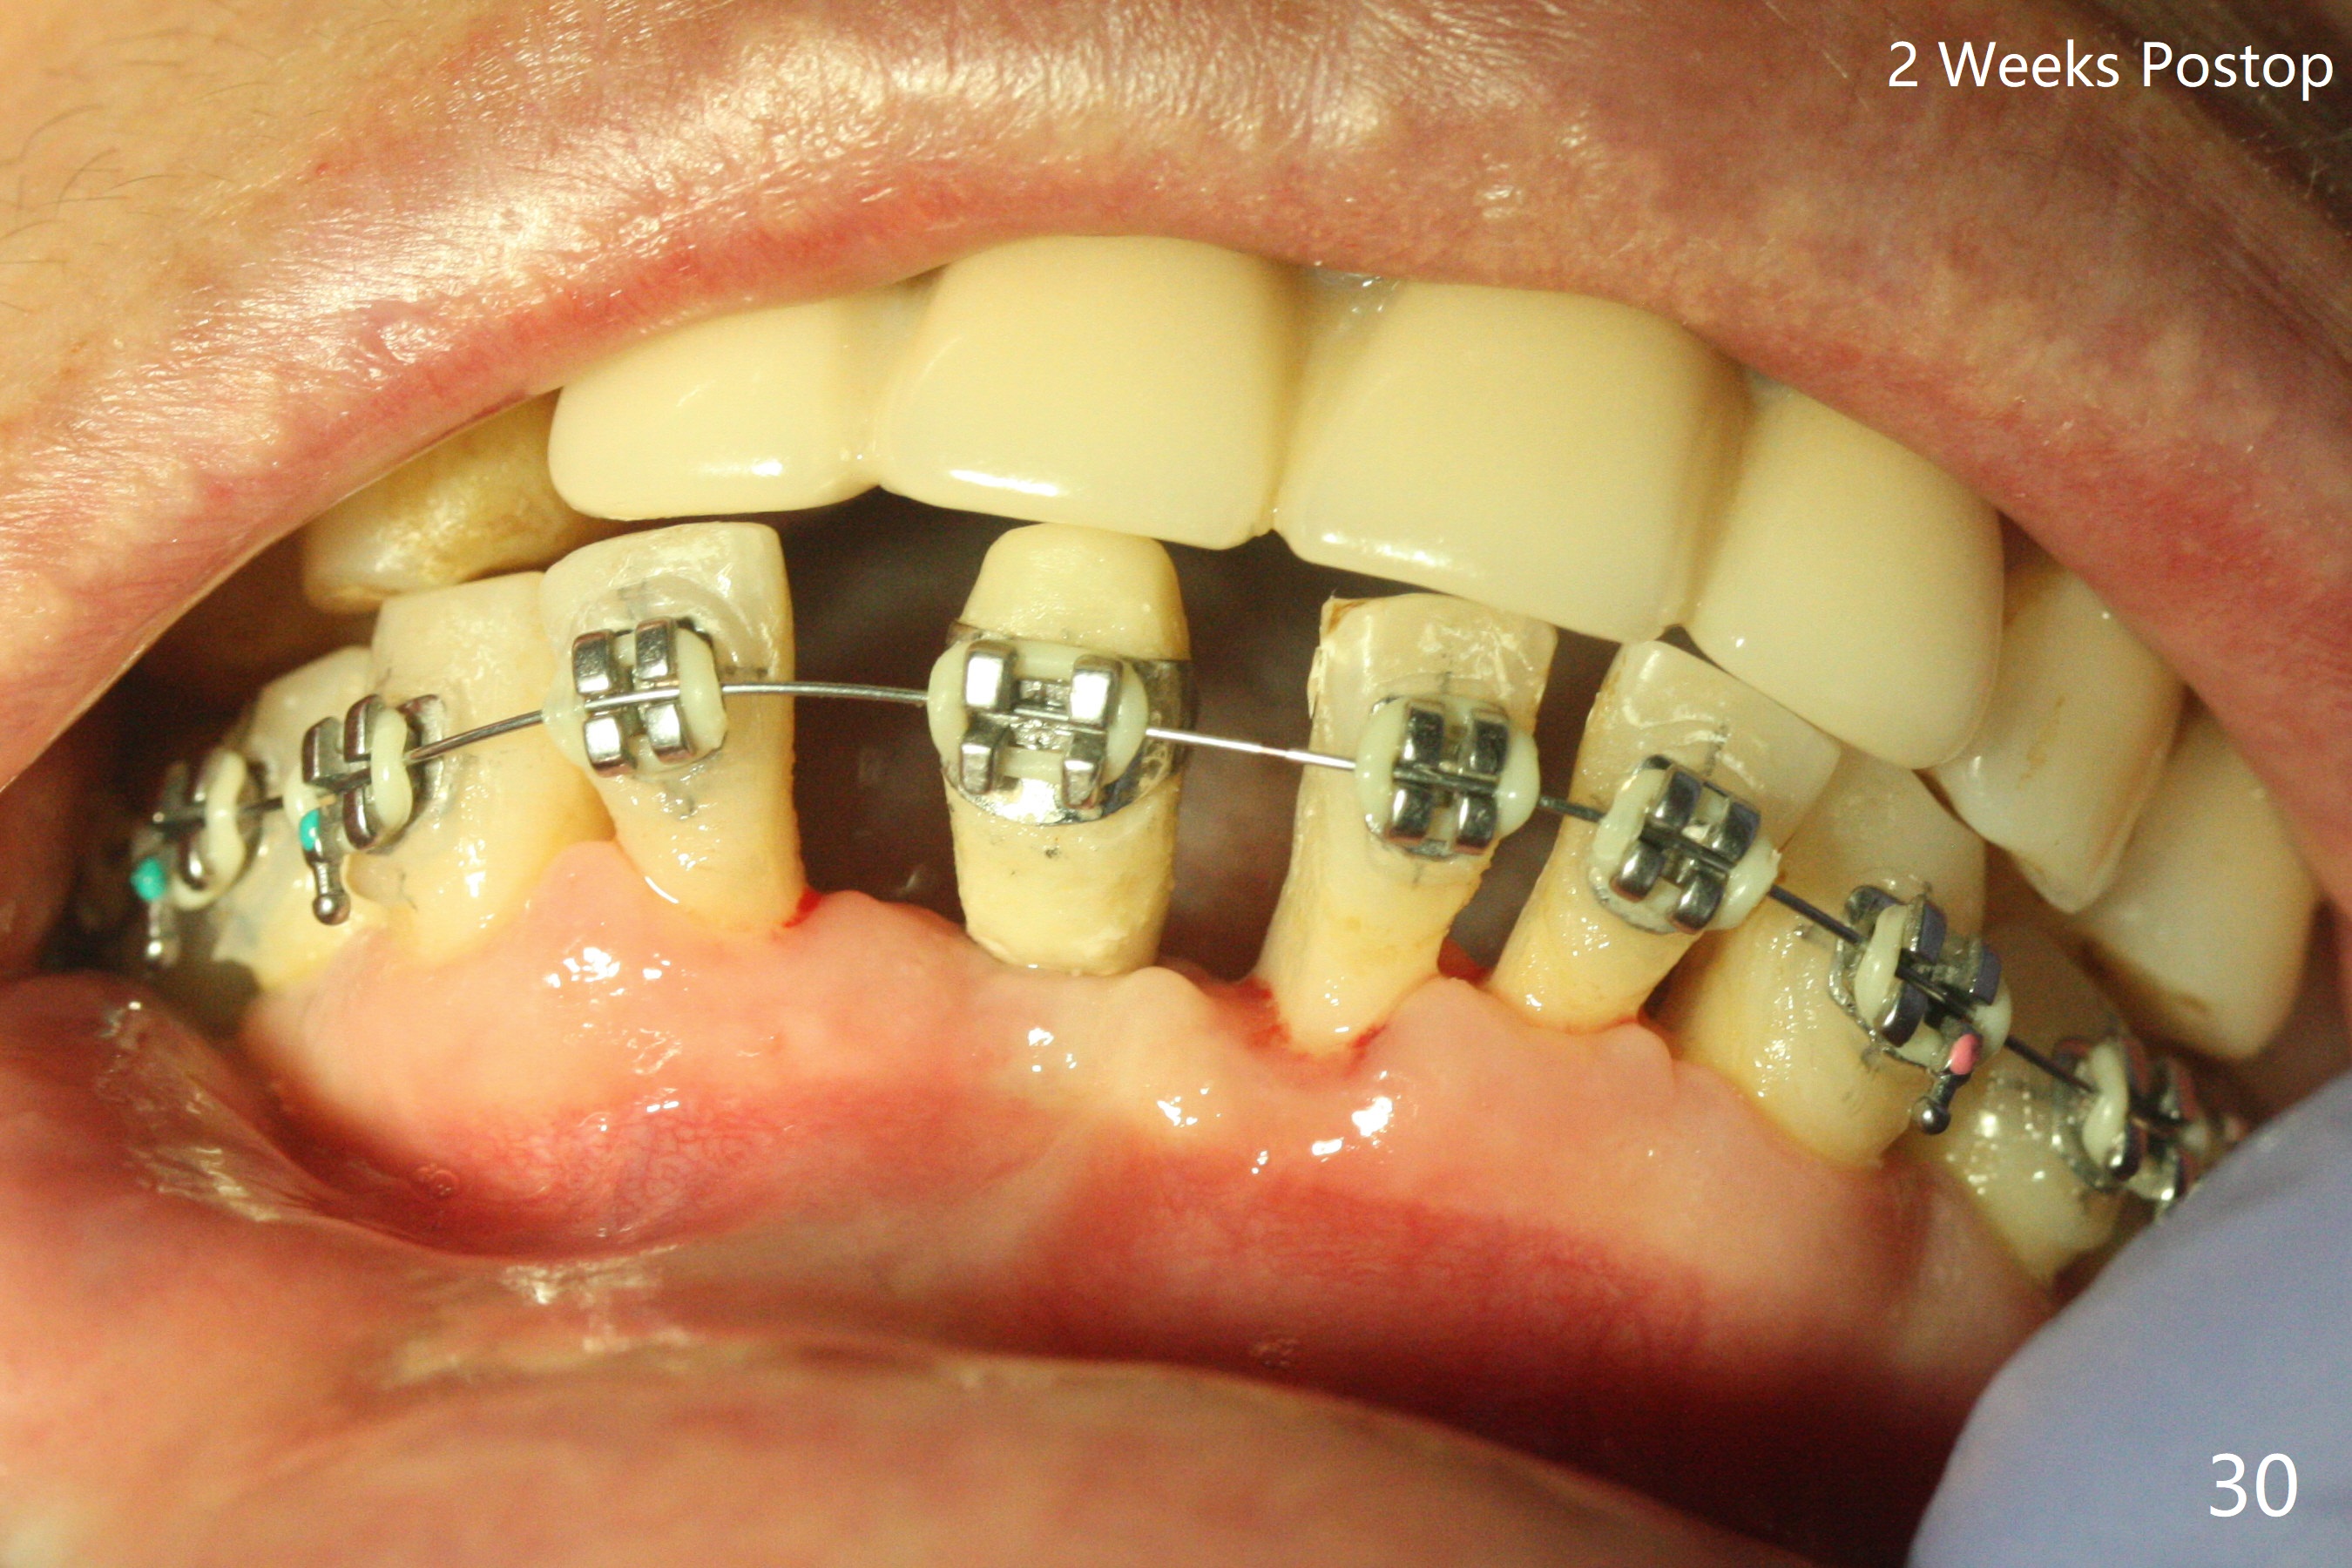

56岁女十分恐惧治疗,缺失右下1,其余切牙由于骨质吸收颊侧移位(图一:1,2),但是她不愿意拔除,同意右下1种植,牙周骨手术,植骨;植体整合后作为支抗,矫正移位下门牙。为了防止忘记舌侧瓣分离,先做舌侧切口(图二),然后颊侧瓣松弛分离(图三),包括使用前牙隧道刀(图四)切断颊侧骨膜,松弛到颊侧瓣能向舌侧牵拉3-4毫米(图五),舌侧瓣骨膜下广泛,深部分离(好像不能切断骨膜,图六),放置导板,磨平狭窄的牙槽嵴(图七:O(osteotomy)),植入2.5x12(4)毫米一段式植体(图八:故意舌侧植入,以便以后矫正),在颊侧骨板打多个出血洞(图八:箭头),然后把在平的器皿上形成的粘性骨板(sticky bone,图九),放置于植体和移位切牙周围(图十),接着使用消毒过的橡皮障punch(图十一(纸头相当于PRF膜;事先给助手示范))在三个PRF膜(图十二)打洞,套在植体和门牙上(图十三: 箭头),防止膜(图十四)和骨块(图十五,十六:*)移位,最后还必须使用最原始方法牙周敷料保护伤口(图十七)。术后9天,舌侧牙周敷料脱落,伤口稍微裂开(图十八)。术后18天撤除敷料,伤口裂开处有新鲜肉芽组织生长(图十九(*:下面是填入的骨粉,将是增宽的牙槽嵴(如果你是乐观主义者)),二十)。病人十分感激我们帮助她度过难关。她的确有sleep apnea,否定tongue thrust。术后三个月植体周围没有明显骨质吸收(图二十一至二十三),左下1,2轻度反合(图二十四),植体周围软组织健康(图二十五),5-5安置矫正器(图二十六,二十七,12 niti)。一周后下切牙向舌侧移动(图二十八),左下1,2反合纠正(图二十九)。再一周变化不大(图三十),植牙圈有些松动,两周后将重做临时牙冠,槽往舌侧移动。结果病人提前回来,植牙槽舌侧移位。一周后右下2不适(图三十一),尝试近中牵引(图三十二)。